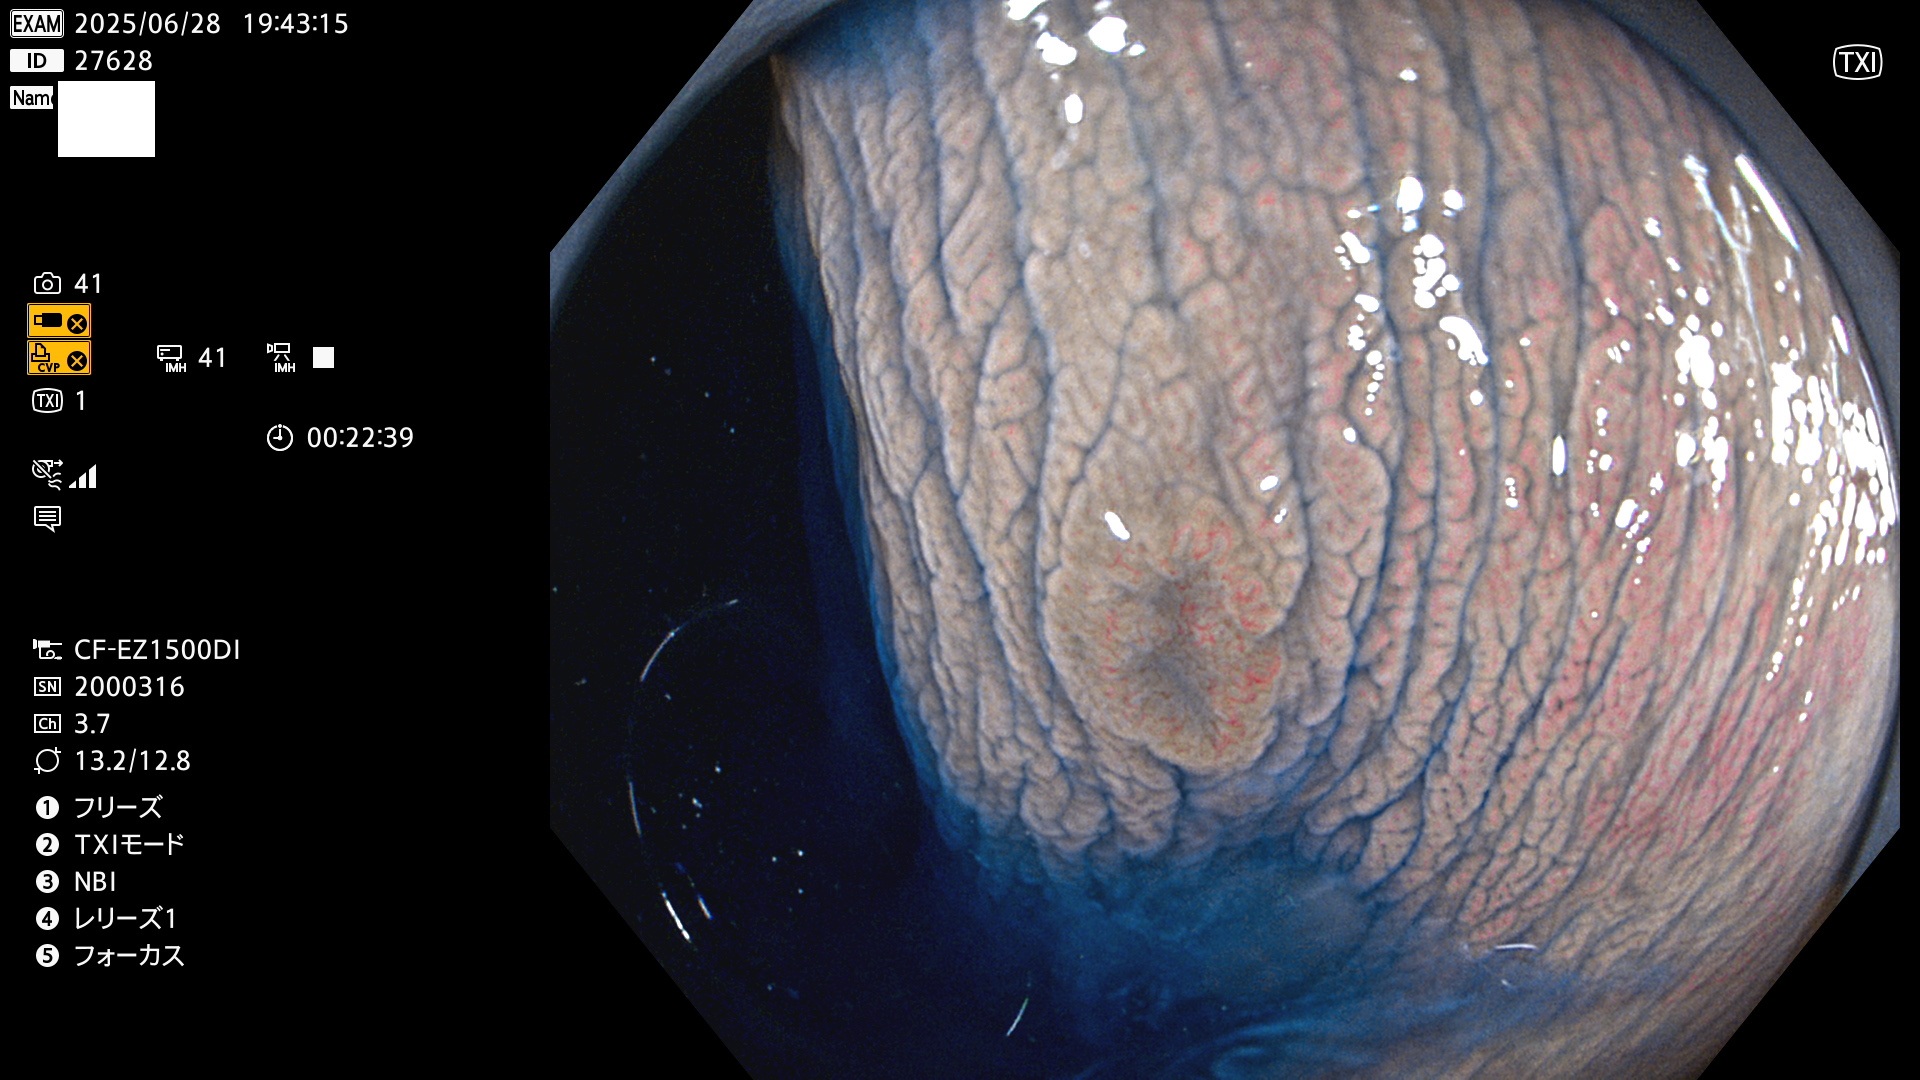

今週のUb、Uc型腺腫

完全に平坦な物をUb、陥凹している物をUcと呼びます。Ubは認識が困難で、Ucはびらん(炎症)と紛らわしいために見落とされやすく、「内視鏡後・大腸癌」の原因になります。

毎週の検査(木・金・土・日)に発見されたUb、Uc型・腺腫を、その週の日曜の夜にUPし1週間、提示します。

抽出の対象期間 2025年6月26日〜6月29日の4日間(40件の検査)7個 (7/40=18%)